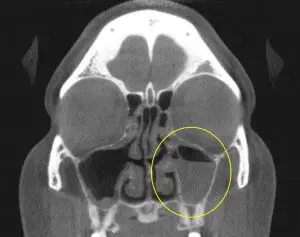

Physical Exam: Clinical and physical exam revealed a component of pressure and discomfort overlying the maxillary(cheek) and frontal(forehead) sinus region. Nasal congestion was worse while the patient would lay flat, contributing to open mouth breathing and snoring at night. A nasal endoscopy was performed revealing evidence of prior sinus surgery. The patient had scar tissue formation that was obstructing normal sinus drainage, likely contributing to the sinus pressure and congestion. An in-office CT Sinus was then performed revealing evidence of prior sinus surgery, but also evidence of impaired sinus drainage and a build-up of significant sinus secretions(PreOp CT Scan). This resulted in an accurate diagnosis of chronic sinusitis secondary to scar tissue build up from prior sinus surgery.

PreOp CT Scan: (2/15/2016)